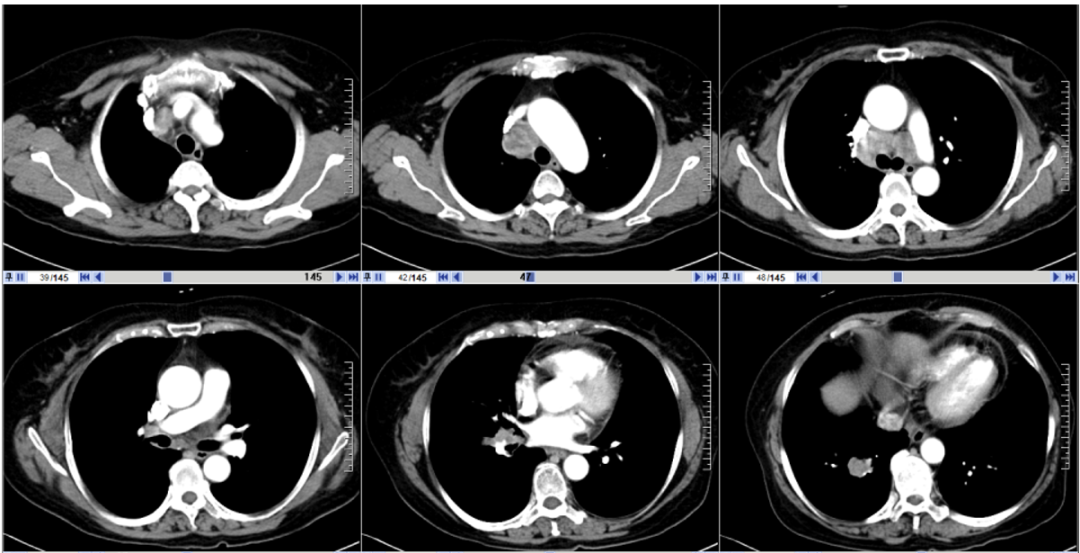

+替雷利珠单抗/安慰剂”治疗5个周期。用药后,肿瘤快速缓解,第一次疗效评估达到PR。2021年4月17日起,进入维持治疗阶段。

图5. CT复查结果

2022年3月23日行头颅MRI:提示头部出现转移病灶。肺部病灶稳定。与试验方沟通后,允许脑部病灶给予放疗,并继续原方案维持治疗。脑部放疗方案为PGTV:45GY,4.5GY/次,5次/周。至此,患者PFS1已达15个月。

2023年6月5日患者出现头部症状重,头脑不清楚,行MRI提示放射性脑坏死。此后患者出组,临床揭盲确认其属于替雷利珠单抗组。

2023年7月给予患者“贝伐珠单抗

联合化疗”治疗4周期后头部症状缓解。后继续替雷利珠单抗维持治疗,期间定期影像学随访,疗效维持PR。

最后一次影像学随访时间为2024年3月22日。此时,PFS2已超过39个月。

图6. 2024年3月22日CT结果

另一例患者为58岁女性,2020年12月体检发现肺占位。经检查确诊为广泛期小细胞肺癌(伴颅骨转移,ⅣB期)。该患者同样入组RATIONALE-312研究,接受“铂类+依托泊苷联合替雷利珠单抗或安慰剂”治疗,首次评估亦达PR。治疗过程中出现颅脑进展,经局部放疗后继续原方案治疗。后因放射性脑坏死退出研究,临床揭盲证实其隶属于替雷利珠单抗组。后续经贝伐珠单抗联合化疗,头部症状缓解后继续替雷利珠单抗治疗,疗效始终维持PR。至2024年3月22日末次随访,其PFS2已超过39个月。